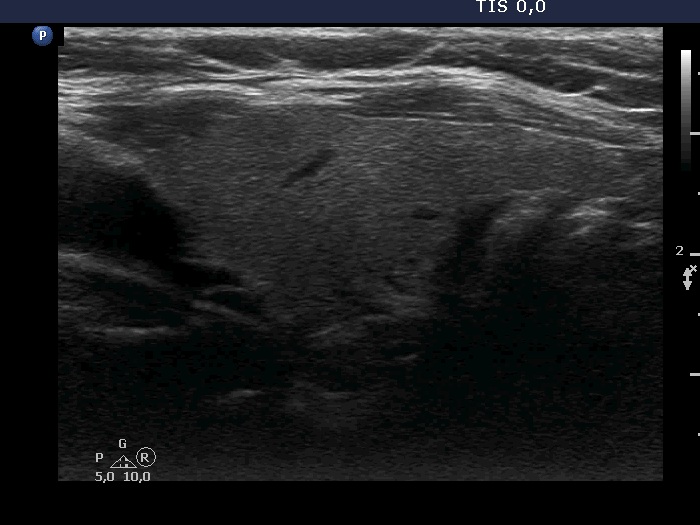

Study on 100 consecutive patients with thyroid nodule - case 034 (ultrasonographic picture 7)

Left lobe, longitudinal scan.